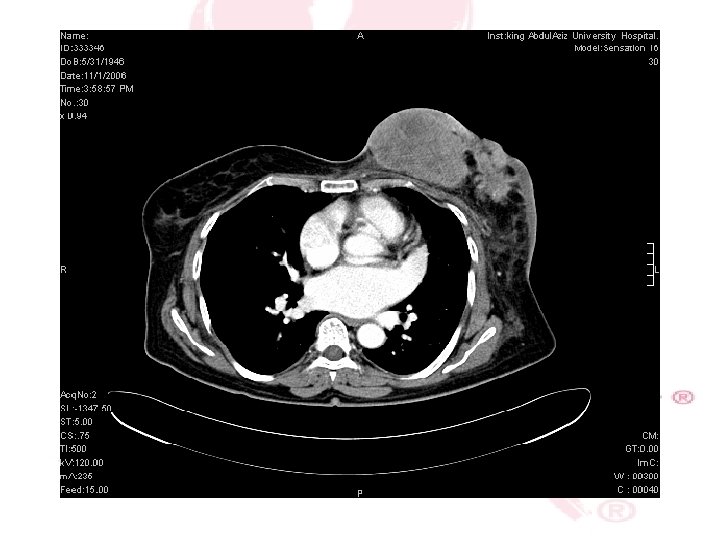

CT SCAN CHEST , ABDOMEN &PELVIS